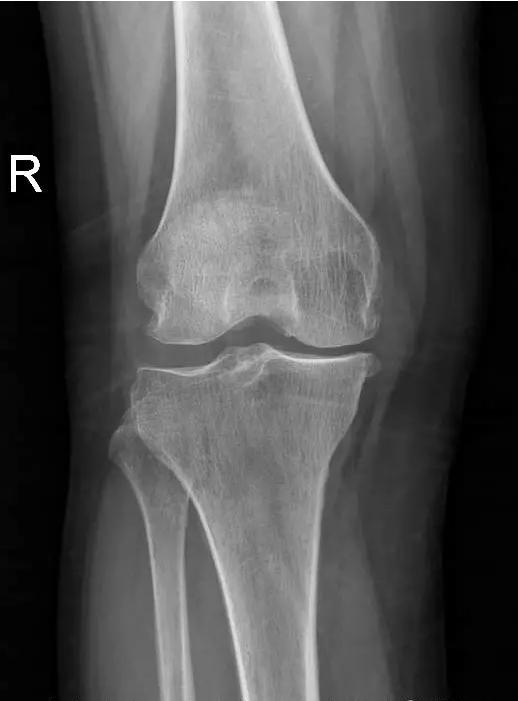

术前片:

对于晚期(重度)骨关节炎,保守治疗无效时,要积极考虑手术治疗。目前效果最佳的手术方式即为关节置换手术,其他手术方式如关节融合手术等效果较关节置换术相差较大,已不在临床广泛使用。关节置换手术的目的是缓解患者疼痛,矫正关节畸形,恢复关节功能,恢复正常生活。对于老年人来说,积极的手术治疗可以有效恢复其日常生活,避免因疼痛及活动障碍导致患者扶拐或坐轮椅,有效减少因缺乏运动导致的心肺功能障碍及精神问题发生。经过几十年的发展,目前关节置换技术已十分成熟,临床上目前采用的微创技术,手术创伤小,术中出血非常少,术后第二天患者即可下地行走,三月之后即可恢复正常生活及功能。至于人工假体使用寿命,目前进口关节多为20-30年,能满足60-70岁患者的需求。需要关注的是,在行关节置换手术之后,患者仍需要进行积极的康复治疗,包括关节活动度及周围肌力的锻炼等,这样才能达到最佳的手术效果。

晚期:骨关节炎表现为膝关节明显疼痛,休息后常无缓解,伴有活动受限,可并发畸形,X 线片可见关节周围有明显的骨赘形成,或可见游离体,关节间隙明显狭窄,甚至消失。